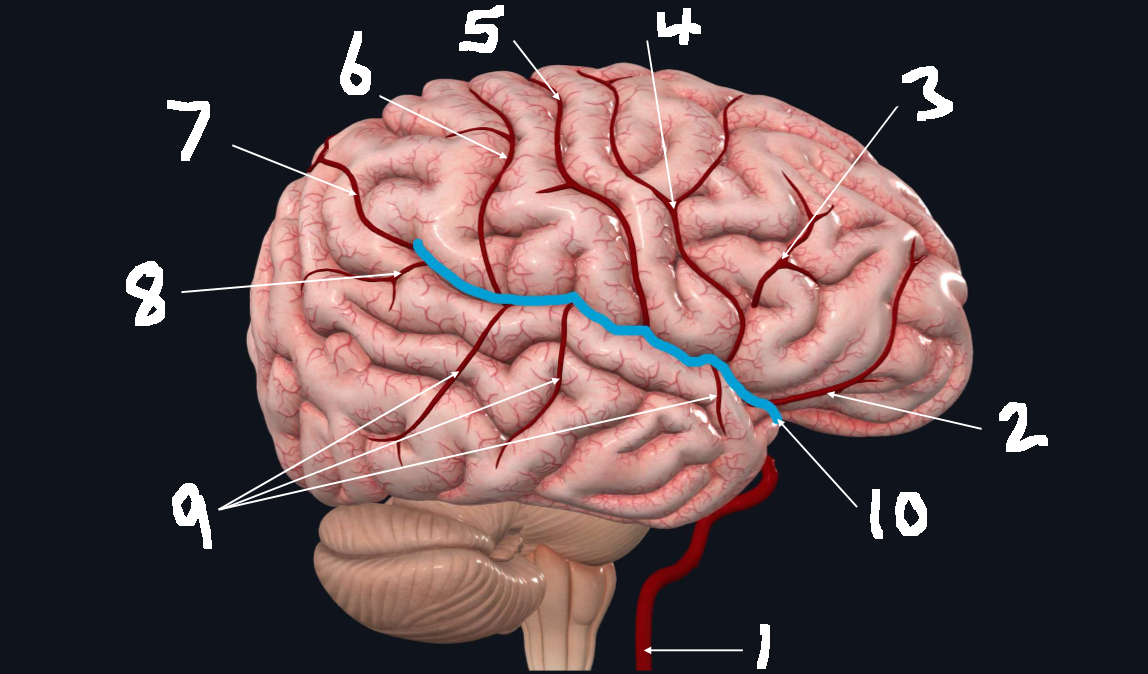

What is 1?

internal carotid artery

What is 2?

orbitofrontal artery

What is 3?

prefrontal artery

What is 4?

precentral artery

What is 5?

central artery

What is 6?

postcentral artery

What is 7?

posterior parietal artery

What is 8?

angular artery

What is 9?

temporal arteries (anterior, middle, posterior)

What is 10?

lateral cerebral fissure